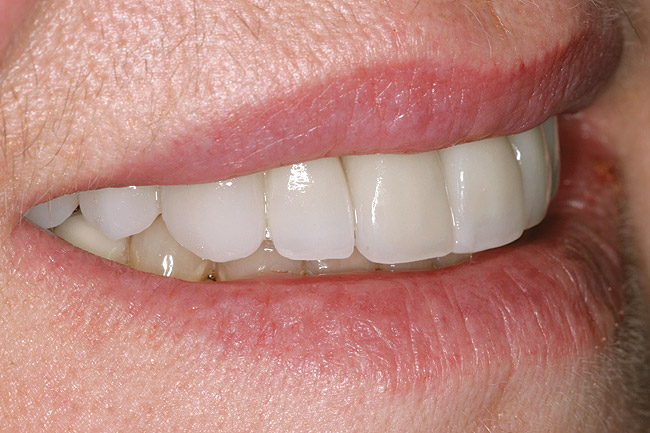

Figure 12 through Figure 14 Final restoration of the severe wear case seen in Figure 9 through Figure 11. The incisal edge position was maintained.

Figure 13

Figure 14

This author has found that a good starting point for the central incisor length is 10.5 mm. The “E” and rest positions are then used to determine the approximate vertical position to place the incisal edge. In many cases involving tooth wear, the patient will want longer-looking teeth. Simply adding length to the incisal to achieve 10.5 mm will often result in encroachment on the envelope of function and the neutral zone. Phonetically, the position of the incisal edge is important when considering the lower lip. The lower lip must interact with the incisal edge in a natural, effortless fashion. This is evident during the pronunciation of words beginning in the letters “V” and “F” (Figure 8). The incisal edge contact should occur in the moist or inner vermilion border of the lip and not the cutaneous or dry portion. This error can often been seen in restorations that are too long incisally.6 The patient in Figure 9 has obviously been occlusally compromised and has extreme wear. However, consider the patient’s current incisal edge location seen in the “E” position (Figure 10). The current position is very close to the ideal vertical position. If an ideal incisor length is to be achieved, the length must be captured from the apical direction. This particular case is an example of passive delayed eruption. As the teeth slowly wear, the alveolar process migrates to keep pace with the tooth loss. The cementoenamel junction, soft tissue attachments, and incisal edge position stay anatomically in place as the process migrates.11 The final restorative process for this patient included hard tissue crown lengthening to recapture added tooth length (Figure 11) and maintenance of the current incisal edge position. The proper maxillary occlusal plane, envelope of function, and anterior guidance were then restored. All of the above parameters were established in the diagnostic phase and then tested in long-term provisionals. The final restorative result can be seen in Figure 12 through Figure 14.